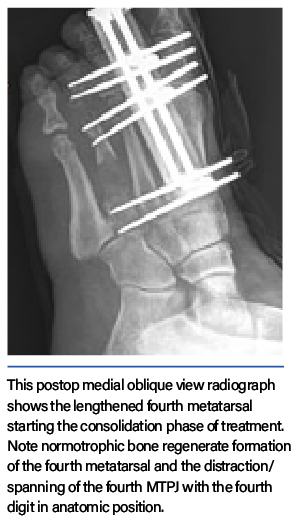

Surgeons have utilized various techniques for acute and gradual metatarsal lengthening, although there are documented complications.1–8 A commonly encountered complication of metatarsal lengthening is metatarsophalangeal joint (MTPJ) stiffness or dislocation/subluxation. To prevent this complication, utilize bridging of the external fixation across the MTPJ during gradual callus distraction.9 In limb lengthening surgery, surgeons have long utilized the concept of bridging the joint to minimize postoperative joint stiffness and contracture.9

Greater lengthening of the bone predisposes the joint to greater forces, which increases the risk of joint subluxation, chondrolysis, and postoperative joint stiffness. Performing the osteotomy farther from the joint lessens the forces that act on the joint, making a proximal metataphyseal-diaphyseal junction ostetotomy preferable. Negative side effects such as cartilage injury to the joint and stiffness in the MTPJ—regardless of how long an axial pin is maintained—can arise when one uses axial pinning to stabilize the digit to the metatarsal head. To prevent postop subluxation, stiffness, and chrondrolysis, the senior author developed a technique of spanning and protecting the MTPJ. The bridging fixator also provides acute digital deformity correction with simultaneous joint distraction, which maintains the long-term mobility of the MTPJ.9-11